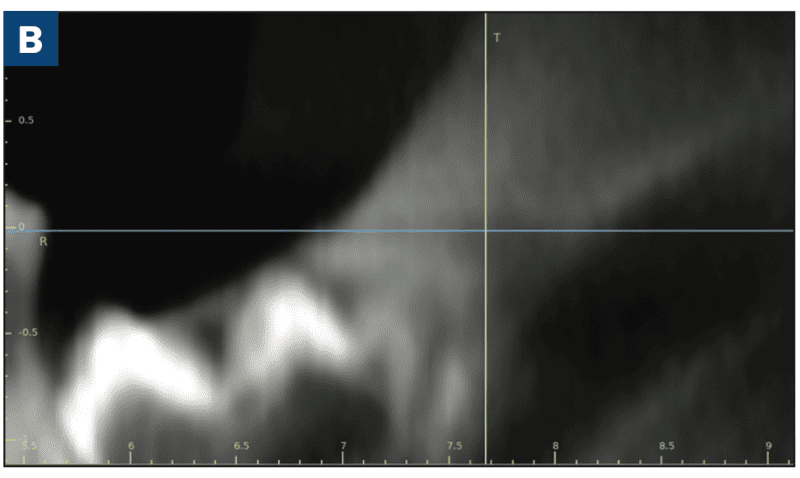

As reported in the April 2023 issue of Journal of Oral and Maxillofacial Surgery, complete molar agenesis was achieved in 100% of TriAgenics’ 3TBA procedures using micro-ablation treatment cycles of 60 seconds or less. Radiographic and histological assessment indicated no presence of treated tooth bud tissue 28 days following 3TBA treatment. Figure 1a shows a typical one-day, pre-operative image of a targeted tooth bud. Figure 1b shows 28-day, post-operative healing results. Histological evaluation at 28-days post 3TBA treatment confirms the presence of complete bony infill with trabecular new bone growth and no detectable viable tooth bud tissue.

Figure 1b. The treated site in Figure 1a (crosshairs) 28 days following 3TBA.